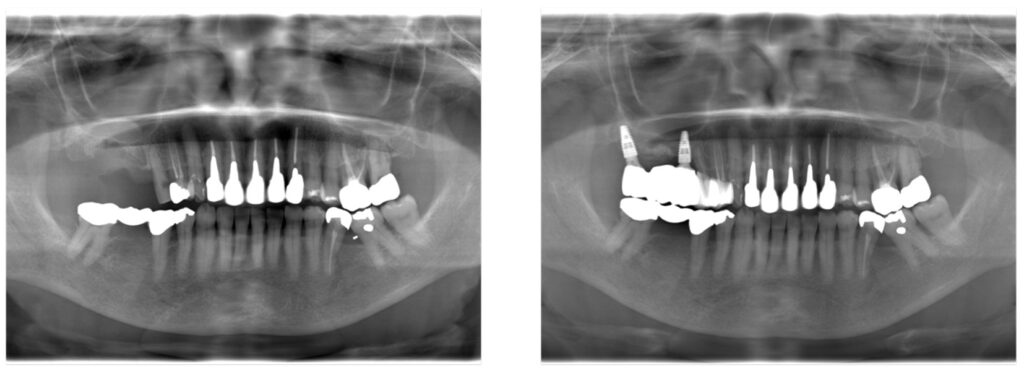

症例39:右上のインプラント治療

ブリッジが壊れて右で噛めなくなった

インプラント治療する

3ヶ月

100万+税(インプラント2本)

審美面を大幅に完全させるとともに、しっかり噛める咬合関係の確立。